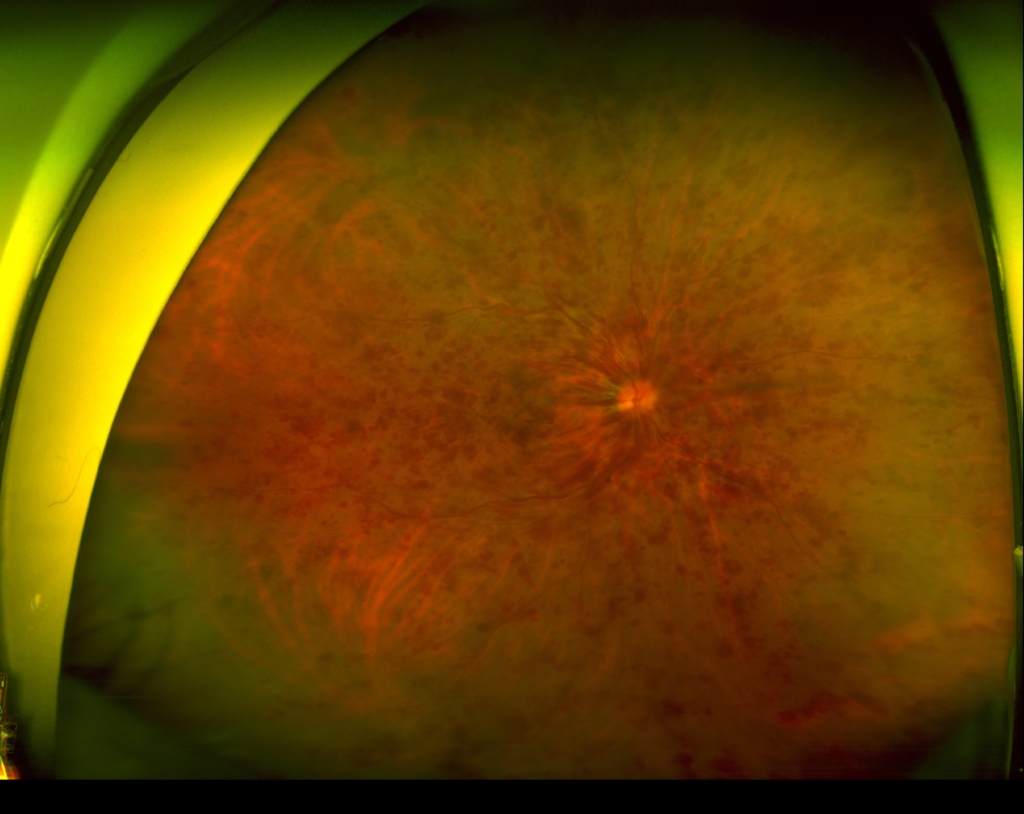

視神経乳頭中心に放射状に静脈に沿って火炎状・線状出血が網膜全体にみられる。